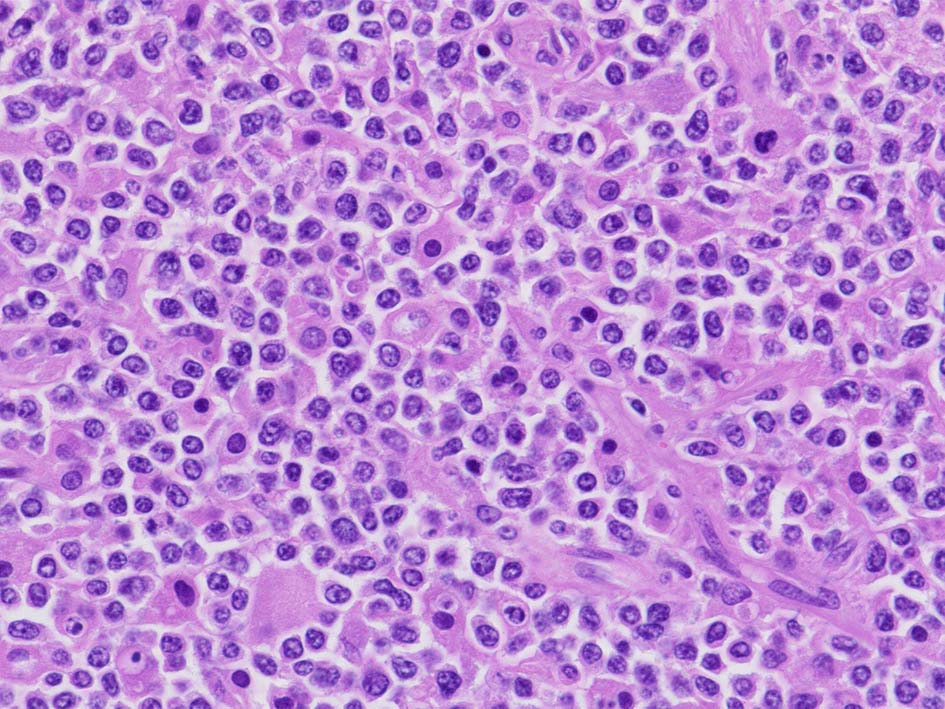

類円形/多稜形の核をもつN/C比大の細胞. 粗大なクロマチンが増加, 核小体は不明瞭. DLBCLに認められるcentroblasts/ immunoblastsの細胞所見と異なる.

LCA(CD45)+, CD20+(focalに陰性), CD79a+, PAX5+, CD5-, CD10+, BCL6+が多い, MUM1-, BCL2+, cyclinD1-, MIB1 LI; very high(>80%). EBER-ISH-.

IGH; clonal band+ (BIOMED2, FR1 and FR2). MYD88L265PはAS-specific PCRで陰性. Molecular にもcommon typeのtesticular DLBCLとは異なっているようである.